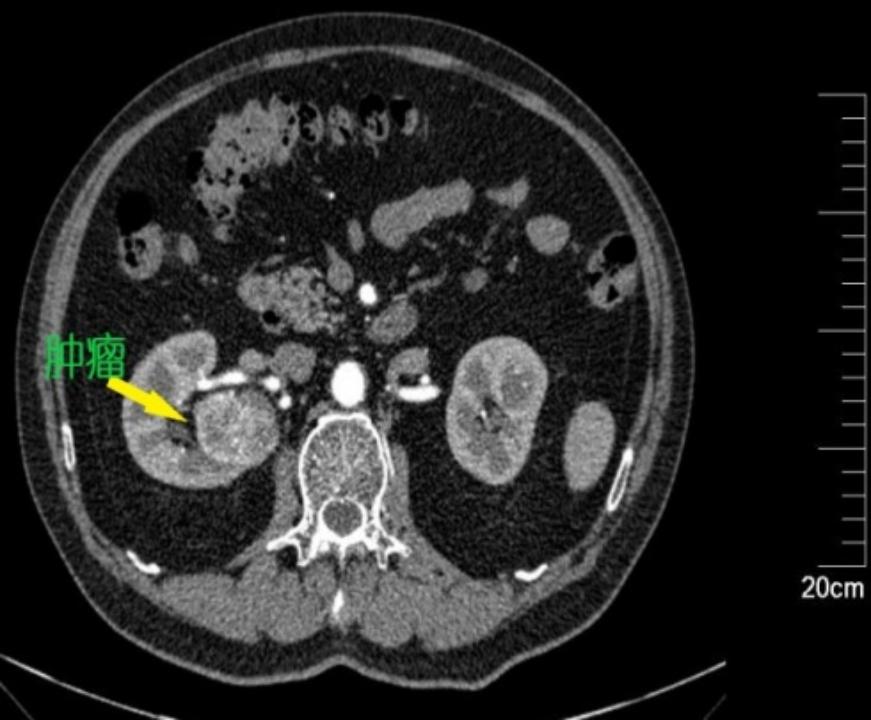

肾动脉CTA:右肾占位,大小约4.7*4.5cm,类圆形低密度影,增强扫描呈不均匀强化,考虑恶性;右肾动脉分支供血。

患者老年男性,体检发现右肾占位,肿瘤最大径约4.7cm,影像资料显示肿瘤位于右肾背侧上极,紧贴肾门处,底部一支肾脏动脉分支环绕。这个位置对于保肾手术来说是一个极其不利的位置,经腹腔或经后腹腔途径来游离暴露肿瘤都不会太方便,肿瘤几乎位于视野的盲区,难以得到充分的操作空间。患者基础疾病多,为保肾慕名而来,任善成主任评估患者病情,制定手术方案:机器人辅助腹腔镜经腹右肾部分切除术。

1.游离动脉:结合术前影像资料,有2支右肾动脉直接从腹主动脉发出,都是肾脏的主要血管,越过腔静脉后走形于右肾静脉偏下方的位置,因此我们在右肾静脉下方寻找到两支右肾动脉并分别予以游离标记。